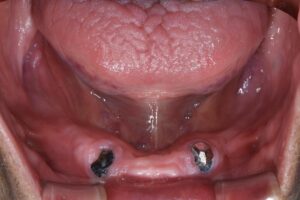

【治療後の下顎のお口の写真】

歯周外科・根管治療などを施術し、ご希望通りの状態まで完成することができました(*^-^*)